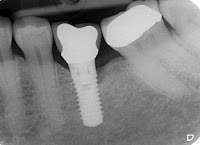

Adequate baseline radiographs determine the peri-implant

bone status as well as the marginal bone level. These can then be compared to

future radiographs to determine if additional bone loss, beyond ‘normal’ has

occurred. Progressive bone loss is a definite indicator of

peri-implantitis.